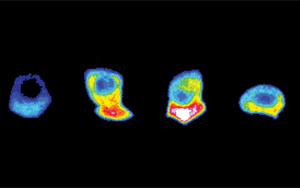

華盛頓大學(xué)醫(yī)學(xué)院(University of Washington School of Medicine)的研究人員表示,與只有疫苗保護(hù)的人相比,在接種疫苗之前感染了SARS-CoV-2的人會產(chǎn)生更具體的免疫反應(yīng),并產(chǎn)生更廣泛的抗體反應(yīng)。